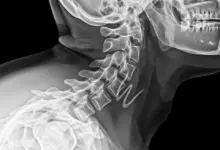

Exames que confirmam

O caminho começa com história clínica e exame físico detalhados. Em seguida, os exames de imagem definem o grau e estabilidade.

- Radiografias AP e perfil, com medidas de Meyerding e dos ângulos.

- Radiografias dinâmicas em flexão e extensão, para avaliar a instabilidade.

- Ressonância magnética, para observar o disco, facetas, canal e raízes.